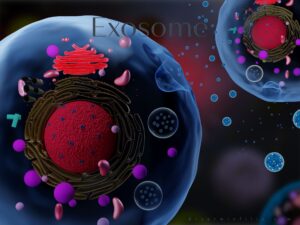

EKSOZOM

Hücrelerden salınan çok sayıda büyüme faktörleri, proteinler ve genetik bilgileri taşıyan nano boyutta keseciklerdir. Hücreler arası haberleşmede görev alırlar. Hedeflenen hücreleri uyararak hücre onarımını sağlarlar.